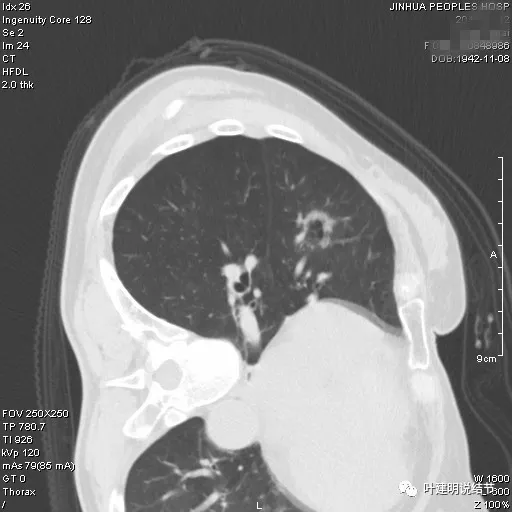

冠状位见病灶基本实性,小血管进入明显,囊壁厚薄不均,囊腔内壁不光滑,表面浅分叶。

矢状位显示较强的收缩力的样子,表面明显棘突的样子,而且囊壁密度杂乱,伴浅分叶征以及胸膜牵拉征。